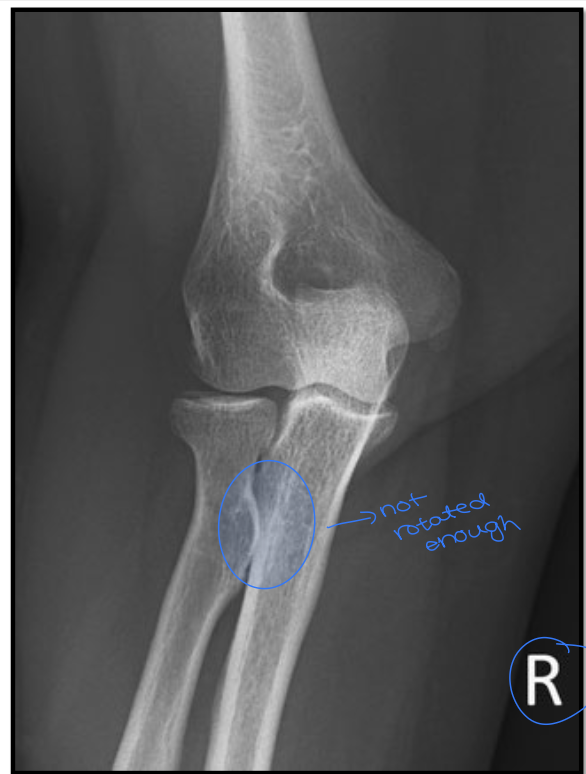

17

Q

What is the positioning fault?

How would you fix it?

A

• under rotated

• radial head not 3/4 under ulna

How well did you know this?